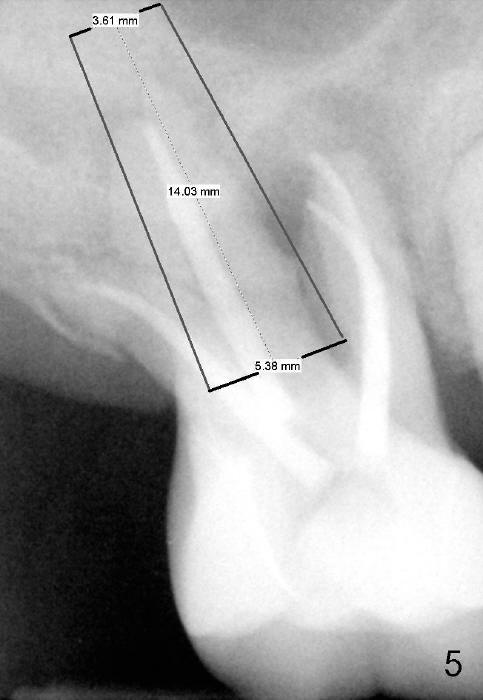

If the septum is basically intact, a 5.3x12 bone-level implant is placed in an ideal trajectory for restoration (Fig.3).  The mesial and distal margin of the implant is at the level of the alveolar crests (arrows); bone graft is placed evenly to cover the coronal threads (red circles). If the septum is defective to some degree, a longer implant is placed distally (Fig.4) with more bone graft placed distally.  Or the implant is placed deeper (Fig.5).  If the septum is severely defective, an extra wide, but shorter implant (6.9x10 mm bone-level SM) is used (Fig.6).  Or an extra wide UF implant with extra 2 mm length may offer better primary stability (Fig.6' (with sinus lift)).  The primary stability of the extra wide implants is derived from contact with the mesial and distal socket walls.